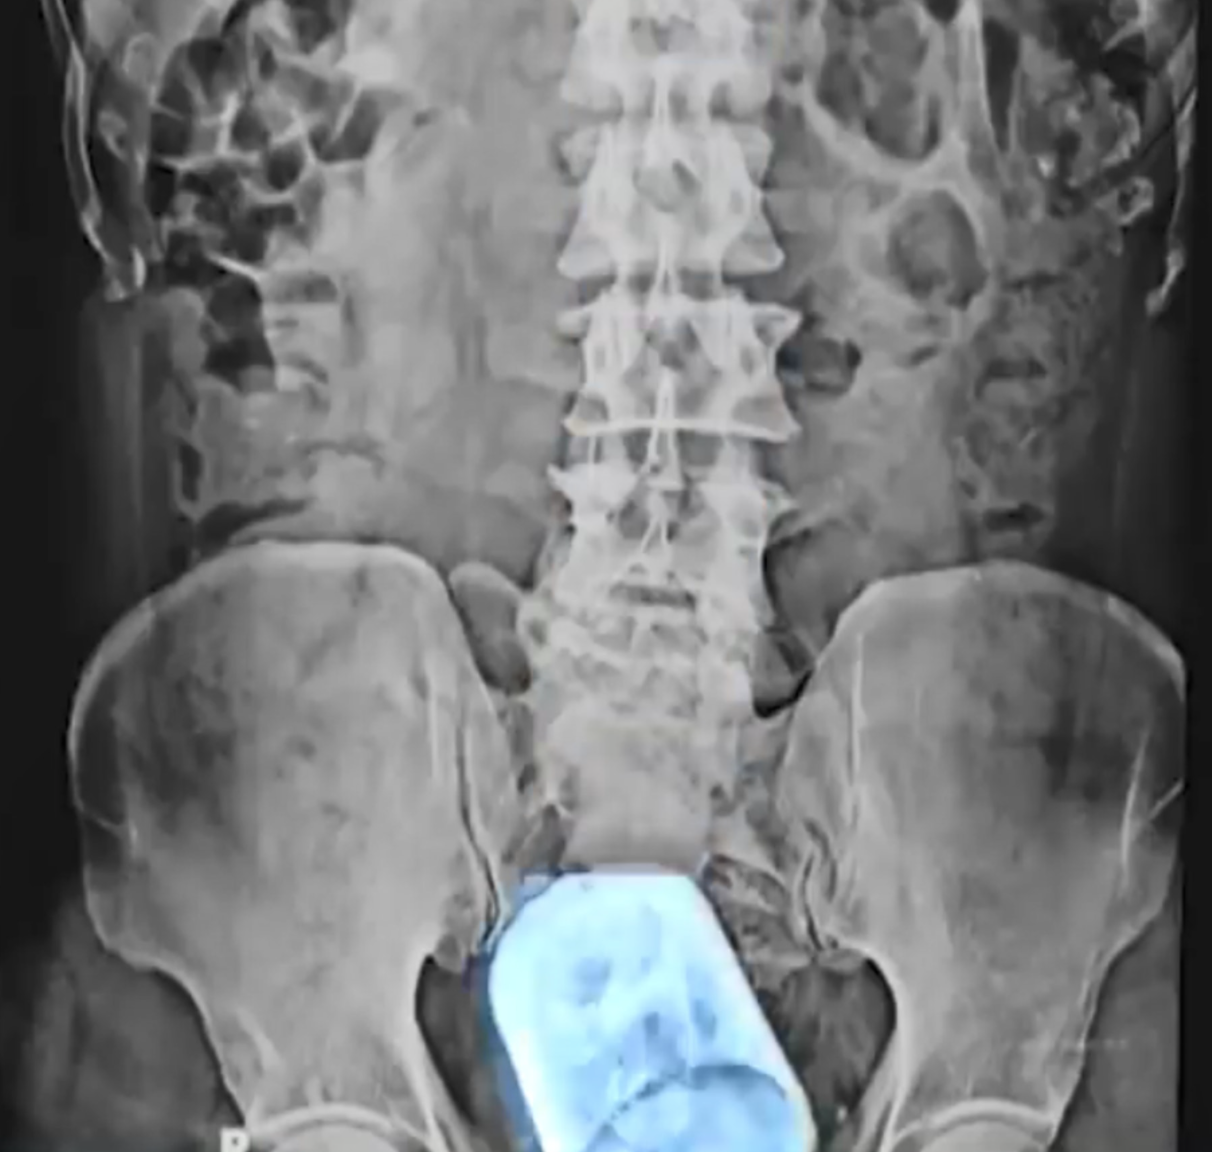

主診外科醫生Mahmudul Hasan表示,從X光片所見,杯子可能比拳頭還要大,男子透露自己是在喝茶時不慎將玻璃杯吞下,醫生指:「這不是個令人信服的解釋,人的食道對這杯來說太窄了。」

醫生最初想通過內窺鏡,將玻璃杯從直腸拉出,然而,由於杯子的體積及玻璃材質問題,最後不得不切開其腹部,再切開腸壁取出玻璃杯。據悉,男子手術後現時情況穩定,但要完全恢復仍需要一段時間。